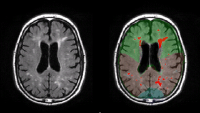

Two brain scan images shown side by side.

Amyloid plaque deposits have been long considered the pathological hallmark of Alzheimer’s disease. Recent research at Columbia, however, has shed light on another important risk marker for Alzheimer’s—"white matter hyperintensities" (WMH).

White matter is a complex wiring system that connects nerve cells in different regions of the brain with one another and affects how the brain learns and functions. WMH are patches of increased signal that show up in magnetic resonance imaging (MRI) scans of the brain.